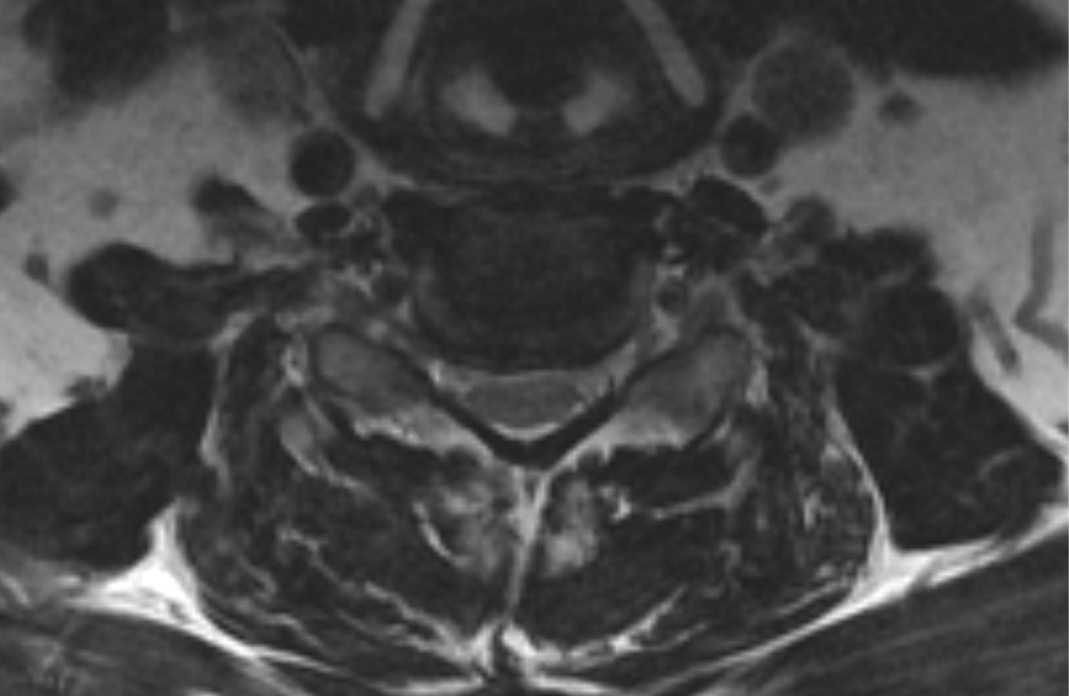

MRIs illustrated mild degenerative disc disease from C4-6 with disc herniations at both C4-5 and C5-6. The axial slice through C4-5 showed a right central disc herniation causing central and mainly right-sided foraminal stenosis. The axial slice through C5-6 showed a central disc herniation also causing central and mainly right-sided foraminal stenosis. The axial slice through C6-7 showed a left-sided disc herniation causing some left-sided foraminal stenosis, however, the patient did not demonstrate any left-sided symptoms.